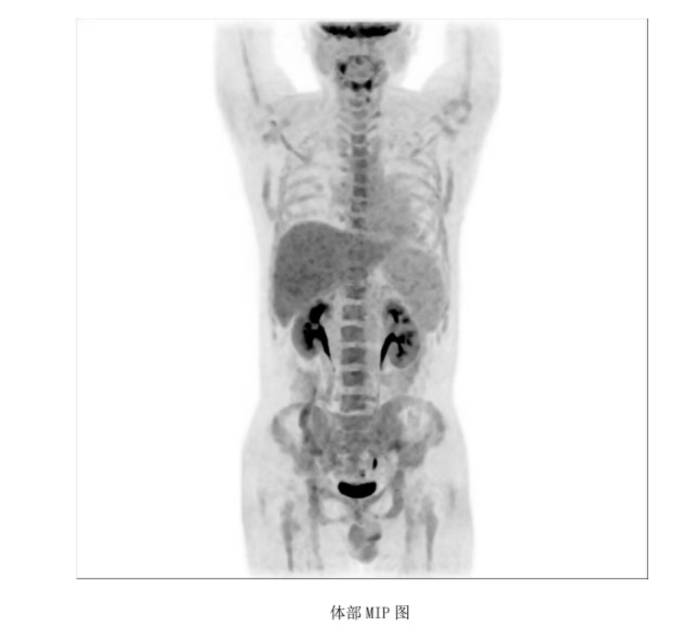

最好的礼物是CR回家过年!我今年38岁,滤泡一直规范治疗但还是转化成弥漫大B淋巴瘤了,双表达型。经过评估参加了16周期的双抗临床试验,可等来的不是完全缓解……而是疾病进展。而且进展的非常快,我喘不上气,躺不平,睡不着。12月初的北京很冷,我觉得这个春节应该是和我无缘了……怀着一丝侥幸希望,我来到了北京陆道培医院。柳喜洋主任看了看我的病历说“你们若信任,我们便全力以赴!”12月3号我们住院了,做了血液和超声等检查。柳主任说我肝功能受损严重,乳酸脱氢酶飙到了2849。双侧胸腔也有大量的积液,左边最深的地方11.5公分。她说那是肿瘤侵犯了多浆膜腔。全身摸得到的地方,淋巴结都是肿大的……柳主任医生团队立刻采细胞,并商量桥接治疗方案,苏敏护士长团队也还一遍遍的安慰我给我加油打气!治疗刻不容缓争分夺秒,桥接后就回输CD19/22 双靶点CART。之后的日子是CART细胞在我体内战斗的日子,我的家人和医护团队也24小时紧张细心的守候着。我也一遍遍的告诉自己要坚持打赢这场仗,我要回家过年!终于回输的第28天,PET CT结果出来了!柳主任洪亮的声音整个病房都听得到:“凯凯恭喜你,CR啦!”曾经那个全身淋巴结肿得像挂了一串串葡萄的我,那个躺不下、睡不着、被胸水压得透不过气的我——被拽回来了。我这医路走来有多少难,心里就有多少的感恩!谢谢柳喜洋主任,苏敏护士长,谢谢所有的医护团队!没有什么比回家过年更好的新年礼物了!小年那天我们在家就吃上了热热乎乎饺子,如今写下感谢的话语,还有送去我的祝福给所有在治疗的病友,祝大家都能CR回家过年!